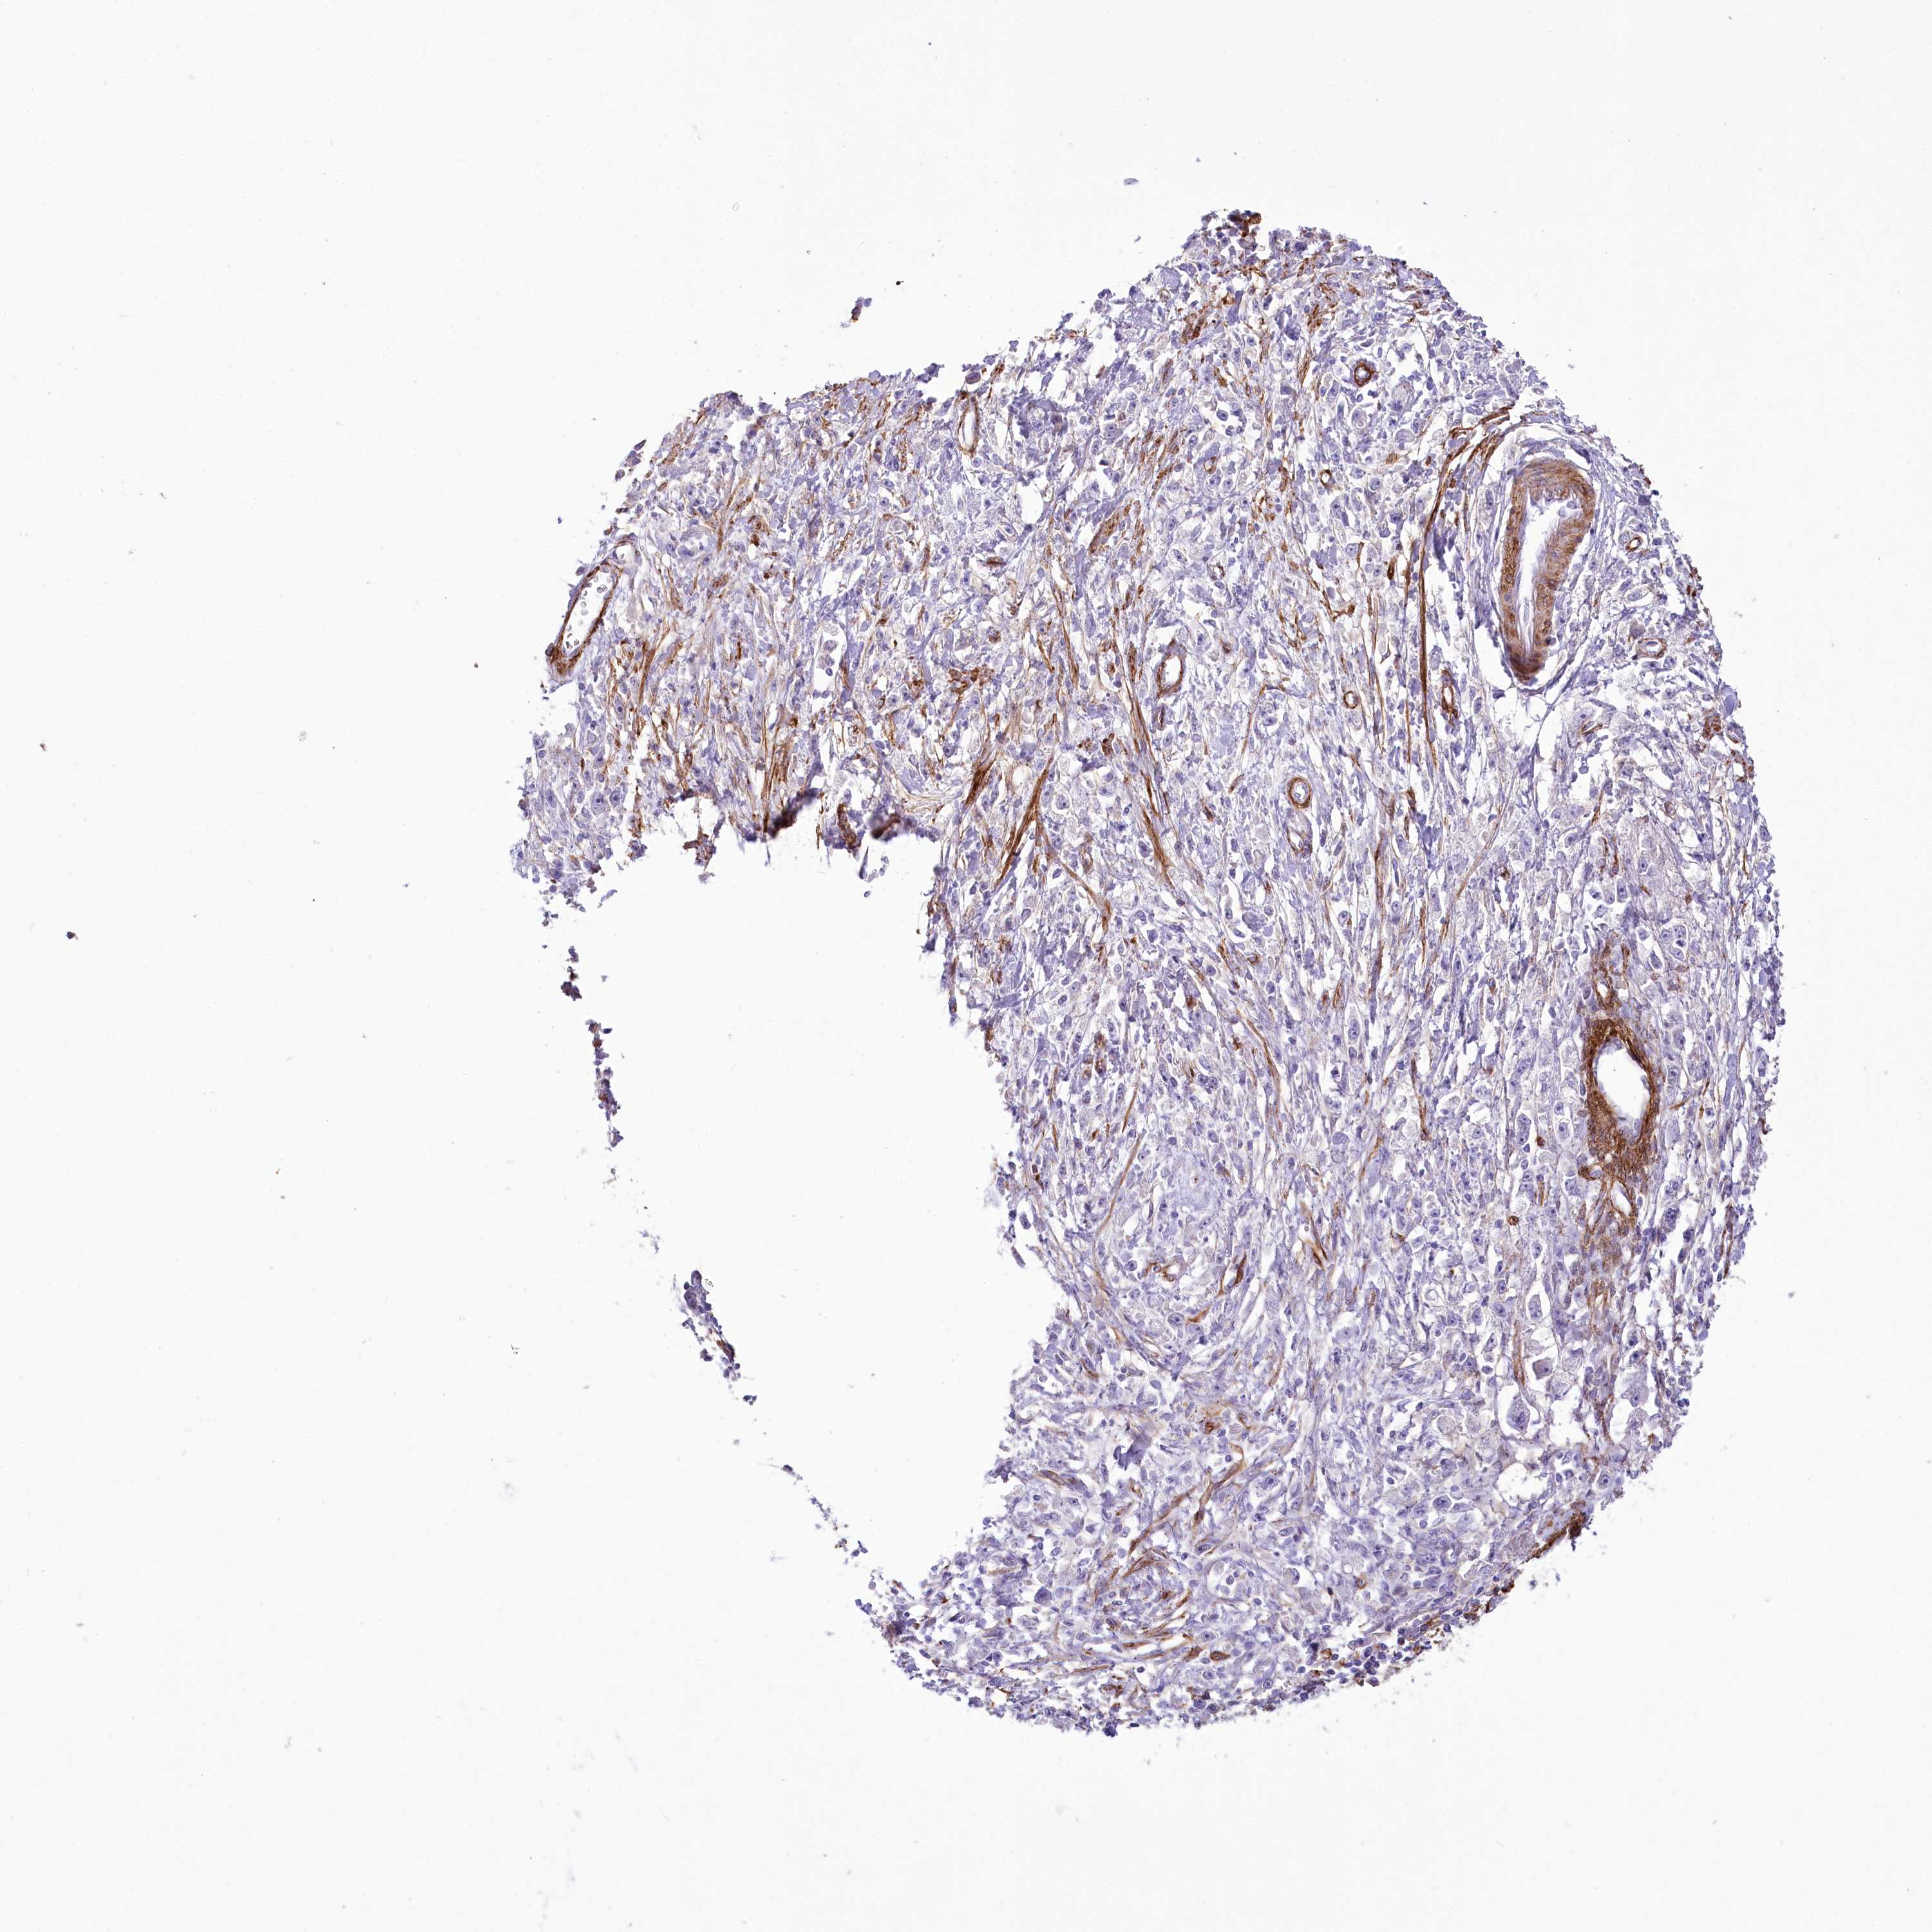

STOMACH CANCER - Protein expressioni

A mouse-over function shows sample information and annotation data. Click on an image to view it in a full screen mode. Samples can be filtered based on level of antibody staining by selecting one or several of the following categories: high, medium, low and not detected. The assay and annotation is described here.

Note that samples used for immunohistochemistry by the Human Protein Atlas do not correspond to samples in the TCGA dataset.

Antibody stainingi

Antibody staining in the annotated cell types in the current human tissue is reported as not detected, low, medium, or high, based on conventional immunohistochemistry profiling in selected tissues. This score is based on the combination of the staining intensity and fraction of stained cells.

Each image is clickable and will lead to virtual microscopy that enables deeper exploration of all samples and also displays staining intensity scores, fraction scores and subcellular localization as well as patient and tissue information for each sample.

Antibody HPA030665

Antibody HPA068563

Antibody CAB037231

Staining

High

Medium

Low

Not detected

Intensity

Strong

Moderate

Weak

Negative

Quantity

>75%

75%-25%

<25%

None

Location

Nuclear

Cytoplasmic/membranous

Cytoplasmic/membranous,nuclear

Adenocarcinoma, NOS